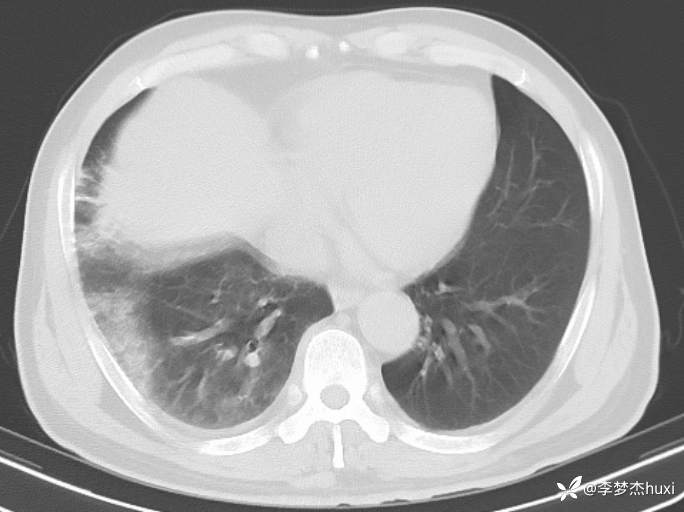

【现病史及既往史】: 1.现病史:患者老年 男,患者缘于入院前4天无明显诱因出现发热,体温最高达38.6℃,无寒战,伴咳嗽,咳痰,为黄痰,胸闷、憋气,周身酸痛,头痛,无咽痛,进食差,无胸痛及咯血,无鼻塞、流涕,无恶心、呕吐,无腹痛、腹泻,无尿频、尿急、尿痛,无血尿及腰背部疼痛,院外口服药物治疗(具体不详),症状无好转,现为求进一步诊治来诊,查头胸部CT:脑干密度欠均匀,双侧基底节区腔隙灶,脑白质稀疏,脑萎缩,鼻窦炎,右肺炎症,主动脉及冠状动脉钙化,双侧胸膜局限性增厚,甲状腺左叶密度欠均匀,建议结合临床复查。查血常规:白细胞数目11.85x109/L,C-反应蛋白241.01mg/L,中性粒细胞数目9.98x109/L,肝功能:谷丙转氨酶108U/L,谷草转氨酶110U/L,心肌酶、血糖、肾功能、钾钠氯、血脂大致正常,尿常规:蛋白质3+,酮体2+,潜血2+。心电图示:窦性心动过速。门诊以“肺炎”收住院。。

4.辅助检查:头胸部CT:脑干密度欠均匀,双侧基底节区腔隙灶,脑白质稀疏,脑萎缩,鼻窦炎,右肺炎症,主动脉及冠状动脉钙化,双侧胸膜局限性增厚,甲状腺左叶密度欠均匀,建议结合临床复查。查血常规:白细胞数目11.85x109/L,C-反应蛋白241.01mg/L,中性粒细胞数目9.98x109/L,肝功能:谷丙转氨酶108U/L,谷草转氨酶110U/L,心肌酶、血糖、肾功能、钾钠氯、血脂大致正常,尿常规:蛋白质3+,酮体2+,潜血2+。心电图示:窦性心动过速。